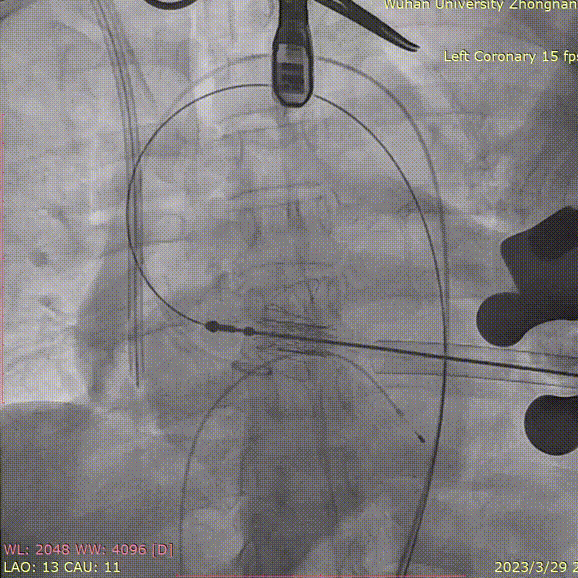

术中造影角度LAO 13°,CAU 11°;主动脉弓、降主动脉及双侧髂总动脉散在钙化,主动脉弓、腹主动脉局部管壁增厚,腹主动脉局部管壁不规则;升主动脉夹层、窦管交界增宽。

定位件于瓣环下打开,将瓣膜件降至合适平面,造影确认:

定位件入窦,造影:

调整导丝,使得瓣膜同轴:

再次造影确定位置: